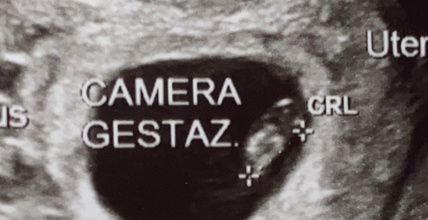

Oggi ho fatto la traslucenza nucale e la dottoressa mi ha detto che il fagiolino era in posizione impeccabile,tanto che il tubercolo si vedeva benissimo e mi ha detto femmina al 100%. Io già da ramzi avevo predetto femmina, ma aspettavo di snetirmelo dire. E così, com'è stato per il primo figlio dove secondo ramzi era maschio, e maschio è stato, anche stavolta ci ha preso 😍 siamo felicissimi, la bimba sta alla grande e si chiamerà VITTORIA. 🌺🌺🌺🌸🌸 Vi lascio l'eco di oggi dove si vede benissimo il tubercolo parallelo alla spina dorsale. Un bacio